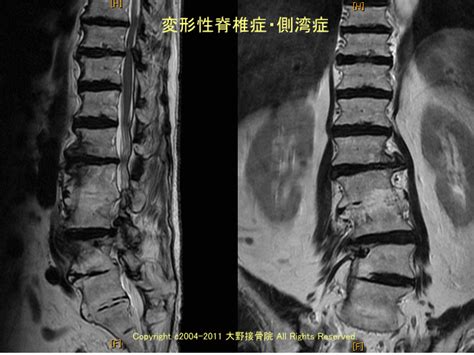

脊椎・脊髄外科領域で最も多い手術症例はこのような腰椎変性疾患です。 olifはoblique lumbar interbody fusionの略で,xlif(extreme lateral interbody fusion)とともに脊椎外科分野において、近年、革命的な進歩をもたらした手術方法です。 Chiari畸形是由於在胚胎發育時期, 小腦下部從頭的後部突出, 進入脊椎管的頸部。 其症狀通常有: 嘔吐, 頭面部肌肉無力,吞咽困難, 和不同程度的精神損害。 甚至可能發生手足癱瘓。

Chiari畸形是由於在胚胎發育時期, 小腦下部從頭的後部突出, 進入脊椎管的頸部。 其症狀通常有: 嘔吐, 頭面部肌肉無力,吞咽困難, 和不同程度的精神損害。 甚至可能發生手足癱瘓。 脊椎・脊髄外科領域で最も多い手術症例はこのような腰椎変性疾患です。 olifはoblique lumbar interbody fusionの略で,xlif(extreme lateral interbody fusion)とともに脊椎外科分野において、近年、革命的な進歩をもたらした手術方法です。

脊椎・脊髄外科領域で最も多い手術症例はこのような腰椎変性疾患です。 olifはoblique lumbar interbody fusionの略で,xlif(extreme lateral interbody fusion)とともに脊椎外科分野において、近年、革命的な進歩をもたらした手術方法です。

脊椎・脊髄外科領域で最も多い手術症例はこのような腰椎変性疾患です。 olifはoblique lumbar interbody fusionの略で,xlif(extreme lateral interbody fusion)とともに脊椎外科分野において、近年、革命的な進歩をもたらした手術方法です。 Chiari畸形是由於在胚胎發育時期, 小腦下部從頭的後部突出, 進入脊椎管的頸部。 其症狀通常有: 嘔吐, 頭面部肌肉無力,吞咽困難, 和不同程度的精神損害。 甚至可能發生手足癱瘓。 脊椎・脊髄外科領域で最も多い手術症例はこのような腰椎変性疾患です。 olifはoblique lumbar interbody fusionの略で,xlif(extreme lateral interbody fusion)とともに脊椎外科分野において、近年、革命的な進歩をもたらした手術方法です。